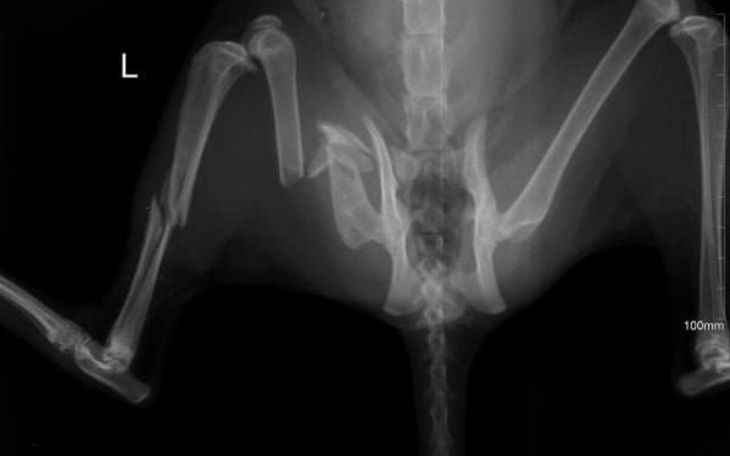

2 tygodnie temu lapalysmy koty które na potęgę się rozmnażaly, trafiło do nas wtedy 11 kotów w tym kotka ktora potrącił samochód

Kotka niestety jest potrzaskana, lekarze stwierdzili że kotce trzeba amputowac nozke, ale po konsultacji z innym lekarzem kotka jest po operacji za którą musiałysmy zapłacić 1 000zl